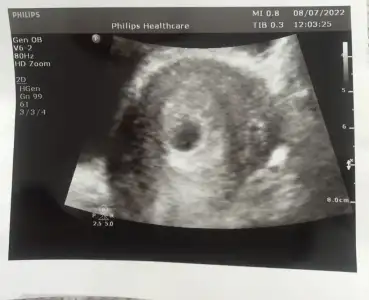

Ben göremedim ama bu görüntüde yazıyor mu ?Evet yazar canm mm olarak

Zannetmiyorum bende bişey farketmedim içi boş siyah bir alan hayırlısı olsun artık bir hafta daha beklicez bakalım ne olcakDoktorun gormustur belki canım sana söylememiş olabilir

Yolk kesesi kesenin içinde yüzüğe benzer hafif parlak beyaz bir şey benim kendi doktorum da bana söylemedi bir gün kanamam oldu acile gittim ultrasona orada ki doktor yola kesesi var dedi eve gelip araştırma yapınca anladım onun varlığı boş gebelik olmadığını gösteriyormuş önce o oluşuyor daha sonra bebekYolk kese de görmedim doktor da bişey demedi

Sağolsun ilgisiz doktorum hiç birşey göstermediYolk kesesi kesenin içinde yüzüğe benzer hafif parlak beyaz bir şey benim kendi doktorum da bana söylemedi bir gün kanamam oldu acile gittim ultrasona orada ki doktor yola kesesi var dedi eve gelip araştırma yapınca anladım onun varlığı boş gebelik olmadığını gösteriyormuş önce o oluşuyor daha sonra bebek